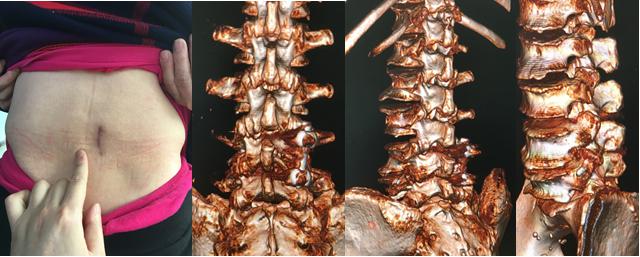

3,术后复查UPS螺钉及TFS螺钉位置佳,融合器位置佳;直抬阴性;切口愈合良好。

螺钉完美

功能良好

4,术后3个月,各项功能良好,行走自如。三维CT重建内固定在位,TFS螺钉完美穿越棘突、椎板、上下关节突和椎弓根。牛骨融合器完整,与植入的自体骨长为一体,发生融合,这种现象在金属及PEEK材料融合器很少观察到,可能说明生物材料的牛骨融合器有促进融合的作用。

切口微创

更令人兴奋的是:仅仅110天左右(3月余),已经明确观察椎体间有明确的大面积融合骨桥形成(从椎体前至椎体后,从左至右均有大面积明确融合),这说明椎体间的融合可能在更早时间已经形成,可能是2个月甚至只是1个月左右就已经有明确的融合发生。

110天融合